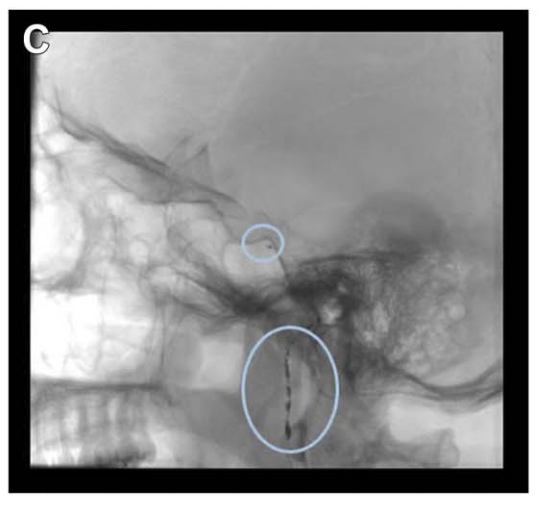

A、B:术后 CT 轴位及矢状位,绿色显示单鼻孔入路,鼻腔完整性得以保持;鼻中隔、上颌窦、后组筛窦及左侧蝶窦间隔均完整。

C:为抵达肿瘤外侧部分,已行左侧颈静脉结节(JT)磨除。

D:蝶窦被颅腔化并以自体脂肪填充,鼻黏膜缝合;肿瘤全切除,未见脑脊液漏。